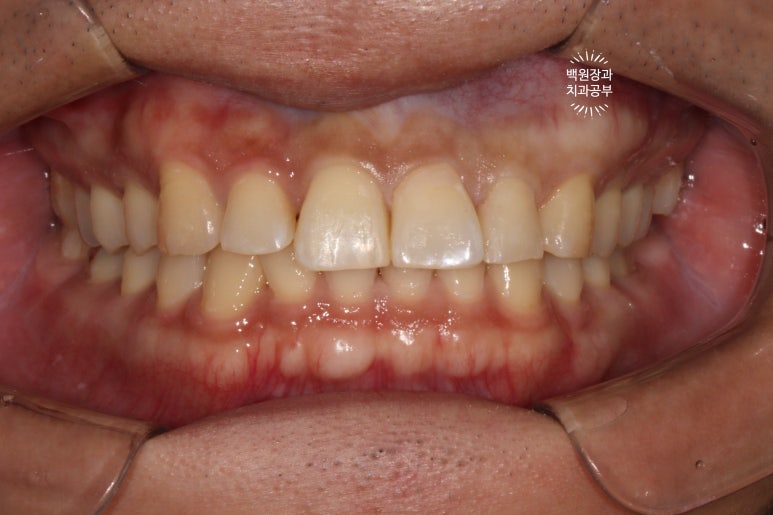

정면으로 보이는 곳은 기존 레진의 변색으로 인한 discoloration이 관찰되었고,

치료를 완료한 모습입니다.

사실 치료 결과는 '당연히?' 완벽해야되겠지만.. 이번 환자분에 있어서 치료 포인트라고 하면, 변색된 레진은 다듬어서 최대한 유지했고 꼭 필요한 부위만 레진충전으로 완료했다는 것에 있겠네요.

가운데 위치한 대문니들은 새로이 레진충전 함으로써 이차우식을 제거하고 깔끔하게 치료해드렸습니다.

어쨌든~ 3M 레진의 자연스러운 색감으로, 아주 만족스러운 치료결과를 얻을 수 있었습니다.